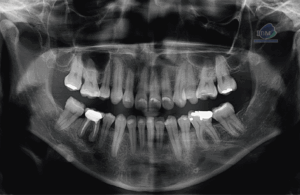

Paciente femenina acude a IDM- Sede Miraflores para evaluar la extracción de terceras molares. Radiografia Panorámica A la evaluación de la radiografía panorámica se observa